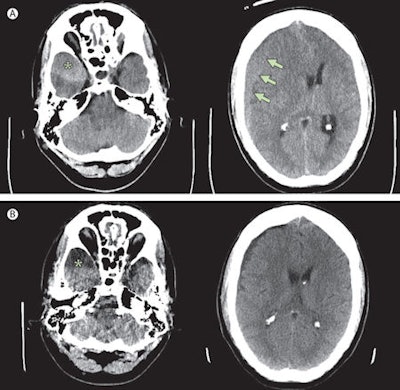

A cranial CT scan confirmed the man had a chronic subdural hematoma on the right side of his brain. Surgeons removed the hematoma through a burr hole and used closed system subdural drainage for six days after surgery. His headache subsided and his last examination two months later revealed he was well (Lancet, 5 July 2014, Vol. 384, pp. 102).

The Hannover case illustrates the impact of headbanging on the development of subdural hematoma, according to Islamian. The patient displayed an arachnoid cyst in the middle cranial fossa; these cysts usually are detected in asymptomatic patients evaluated for unrelated symptoms, and, in a minority of cases, they become symptomatic by, for example, traumatic intracystic or subdural hemorrhage caused by rupture of bridging veins or unsupported veins surrounding the cyst.

The annual risk of hemorrhage within or around the cysts is reported to be less than 0.1%, and although the risk of sustaining a significant head injury with accompanying subdural hematoma is unknown, the chances appear higher in the presence of an underlying congenital arachnoid cyst, he explained. Conversely, the importance of a subdural hematoma as a differential diagnosis in patients with a diagnosed asymptomatic arachnoid cyst showing signs of increased intracranial pressure even after minor head affection is highlighted by this case.